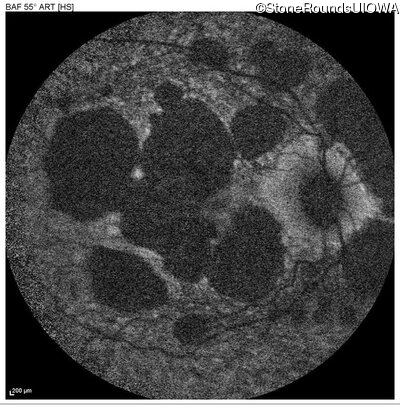

AR Stargardt Disease (IIA)

Age at visit: 51 years

This 51 year old woman first experienced some abnormality in her distance vision when she was 27 years old. She feels that her vision has been stable since that time.

Diagnosis & molecular findings

Disease Gene Allele 1 variant(s) Allele 2 variant(s) Inheritance mode

AR Stargardt Disease ABCA4 Gly1507Arg GGG>AGG IVS42+1 G>A AR